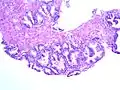

Gleason Grad 3 und 4

Gleason Grad 3 und 4 -